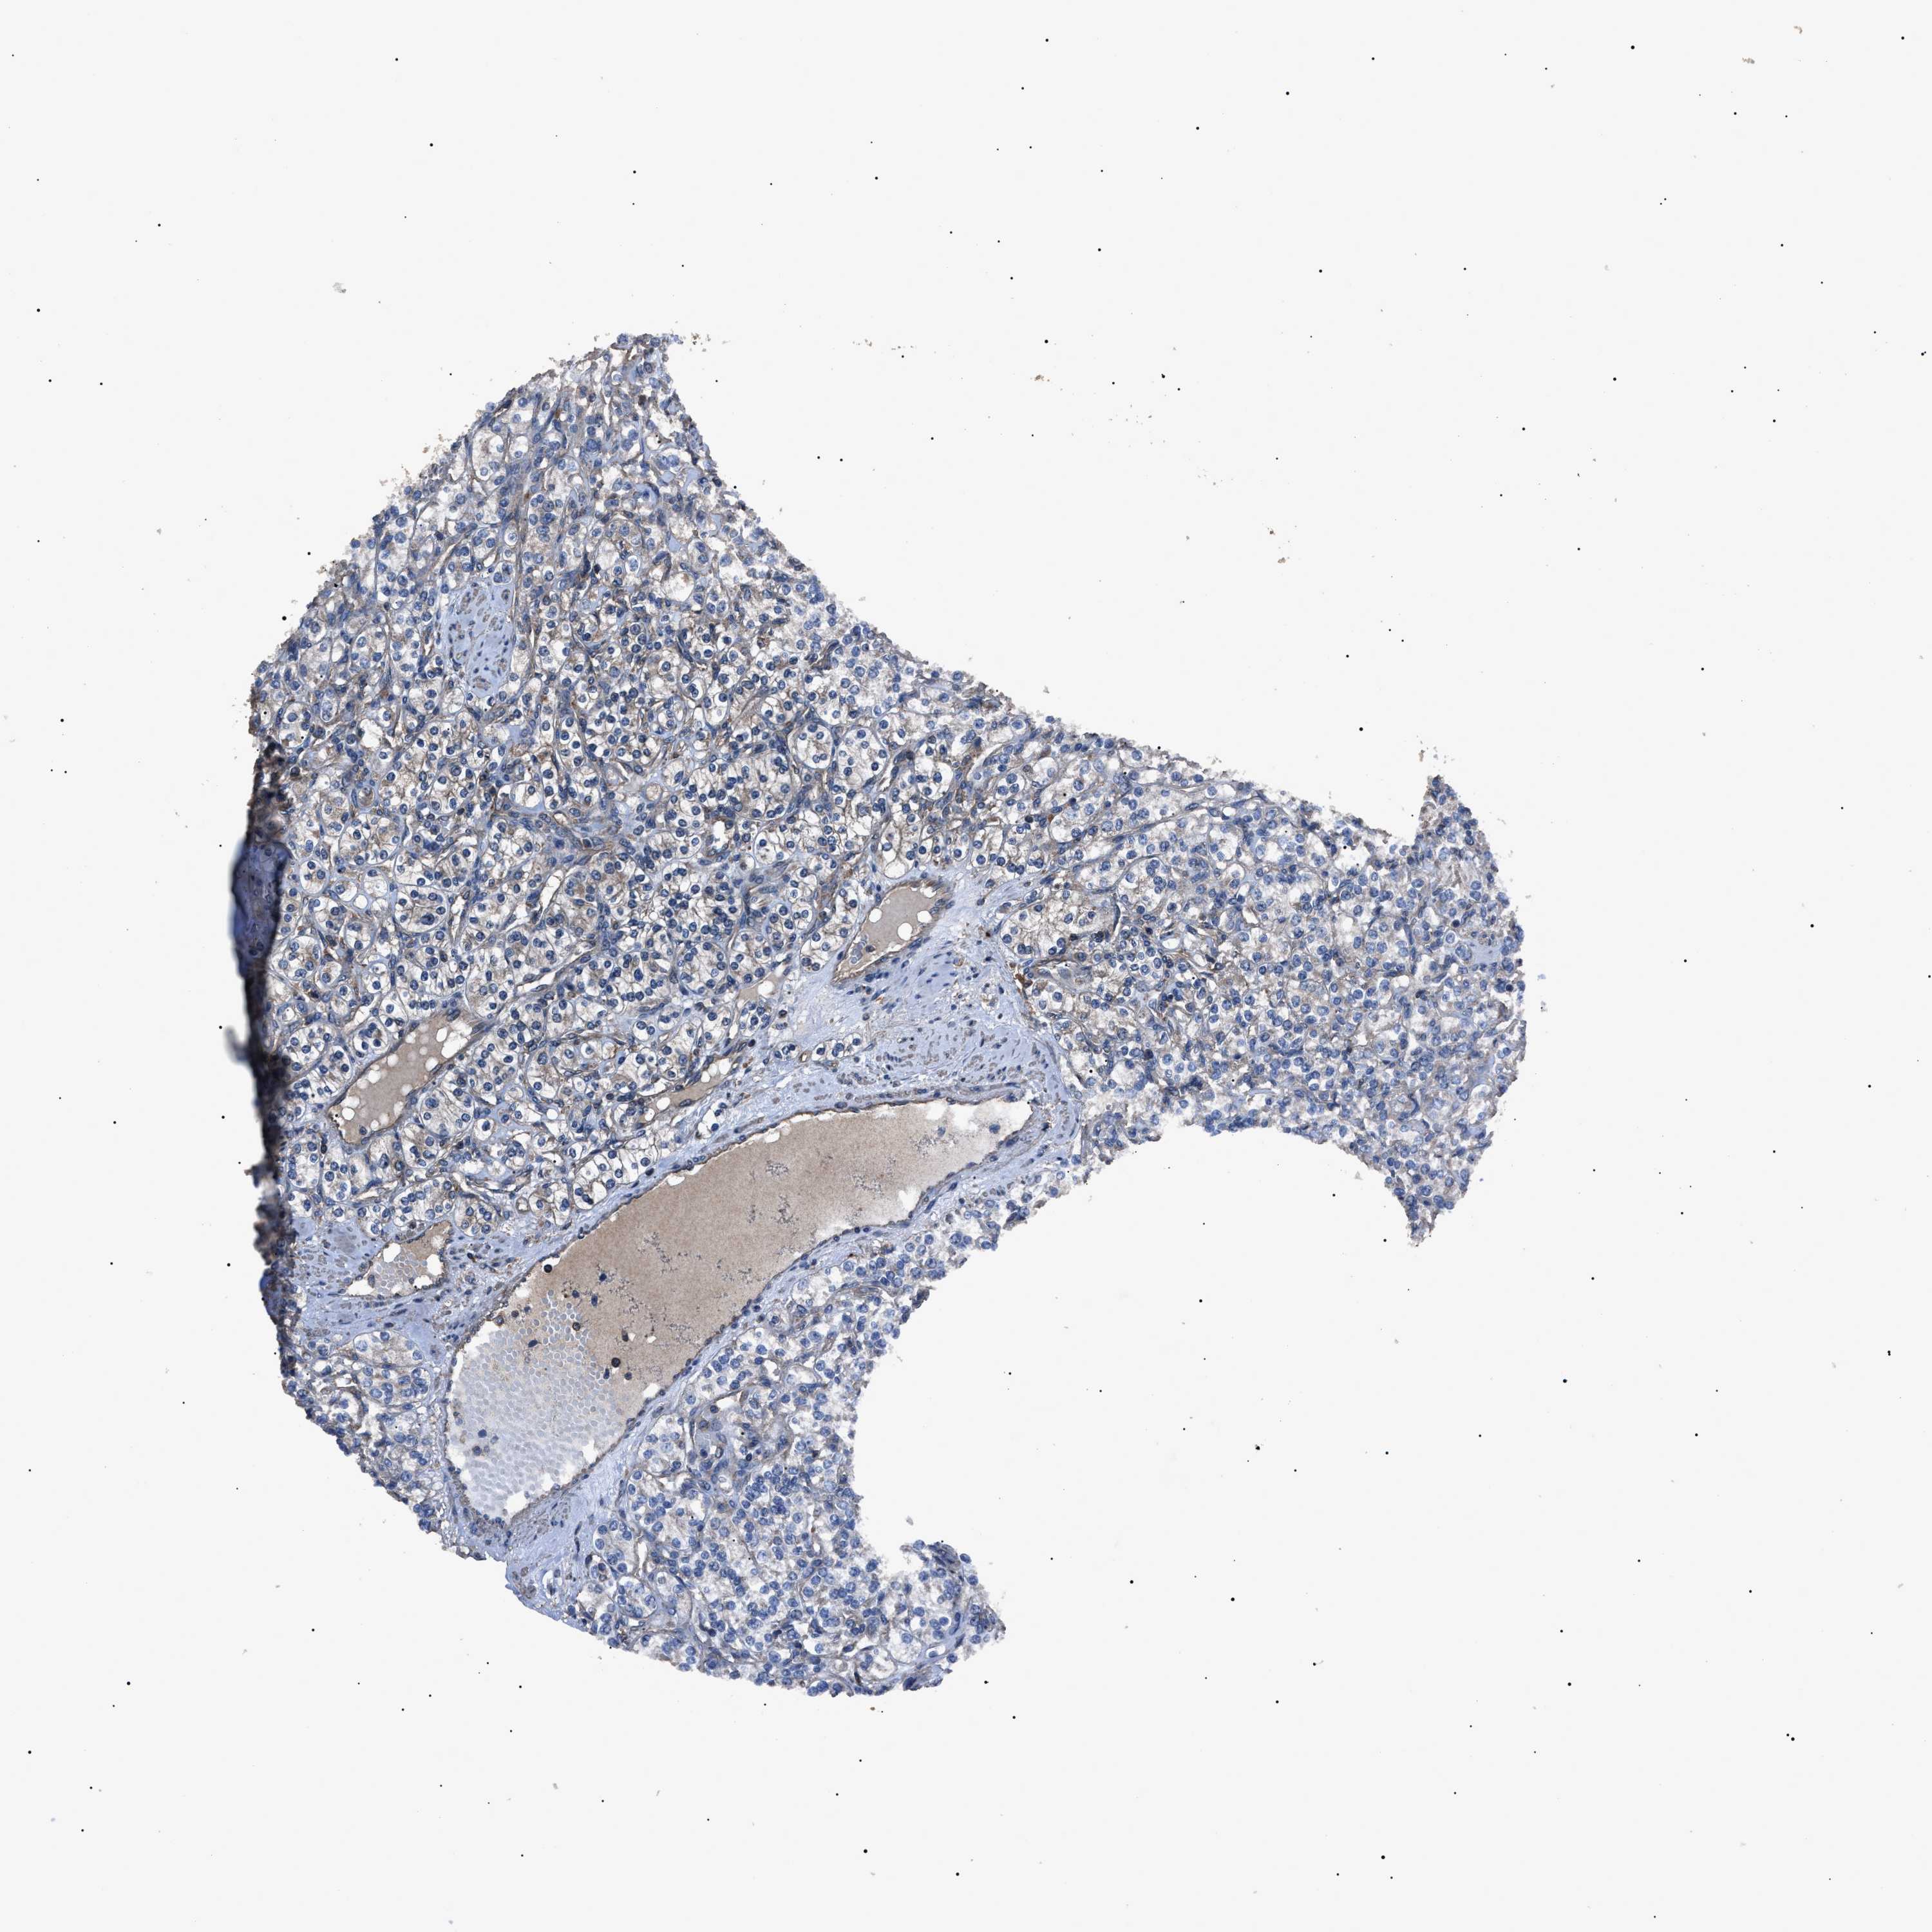

KIDNEY RENAL CLEAR CELL CARCINOMA (VALIDATION) - Interactive survival scatter ploti

The Survival Scatter plot shows the clinical status (i.e. dead or alive) for all individuals in the patient cohort, based on the same data that underlies the corresponding Kaplan-Meier plots. Patients that are alive at last time for follow-up are shown in blue and patients who have died during the study are shown in red.

The x-axis shows the expression levels (FPKM) of the investigated gene in the tumor tissue at the time of diagnosis. The y-axis shows the follow-up time after diagnosis (years). Both axes are complimented with kernel density curves demonstrating the data density over the axes. The top density plot shows the expression levels (FPKM) distribution among dead (red) and alive patients (blue). The right density plot shows the data density of the survived years of dead patients with high and low expression levels respectively, stratified using the cutoff indicated by the vertical dashed line through the Survival Scatter plot. This cutoff is automatically defined based on the FPKM cutoff that minimizes the p-score. The cutoff can be changed by dragging the vertical line or by entering a cutoff value in the square labeled "Current cut-off".

Under the Survival Scatter plot the p-score landscape (black curve; left axis) is shown together with dead median separation (red curve; right axis). Dead median separation is the difference in median mRNA expression between patients who have died with high and low expression, respectively. It is calculated as follows: median FPKM expression of dead patients with high expression - median FPKM expression of dead patients with low expression. This is intended to aid the user in visually exploring custom cutoffs and the associated p-scores and dead median separation.

Individual patient data is displayed and can be filtered by clicking on one or more of the category buttons on the top of the page. Categories describing expression level and patient information include: high, low, alive, dead, female, male and tumor stages. The scale of the x-axis can be toggled between linear and log-scale by clicking on the "x log" button. Mouse-over function shows TCGA ID, patient information and mRNA expression (FPKM) for each patient.

& Survival analysisi

Kaplan-Meier plots summarize results from analysis of correlation between mRNA expression level and patient survival. Patients were divided based on level of expression into one of the two groups "low" (under cut off) or "high" (over cut off). X-axis shows time for survival (years) and y-axis shows the probability of survival, where 1.0 corresponds to 100 percent.

RNF216 is not prognostic in Kidney Renal Clear Cell Carcinoma (validation)

Best expression cut offi

Based on the FPKM value of each gene, patients were classified into two groups and association between prognosis (survival) and gene expression (FPKM) was examined. The best expression cut-off refers the FPKM value that yields maximal difference with regard to survival between the two groups at the lowest log-rank P-value. Best expression cut-off was selected based on survival analysis .

When clicking on this number, the vertical dashed line indicating cut-off, the interactive survival plot, and the Kaplan-Meier curve will be adjusted to show results based on the best expression cut-off.

: 18.74

P scorei

Log-rank P value for Kaplan-Meier plot showing results from analysis of correlation between mRNA expression level and patient survival.

N/A

TCGA RNA samplesi

RNA-seq data is reported as average FPKM (number Fragments Per Kilobase of exon per Million reads), generated by the The Cancer Genome Atlas (TCGA) .

Normal distribution across the dataset is visualized with box plots, shown as median and 25th and 75th percentiles. Points are displayed as outliers if they are above or below 1.5 times the interquartile range. FPKM values of the individual samples are presented next to the box plot.

Average pTPM 15.5

Number of samples 100